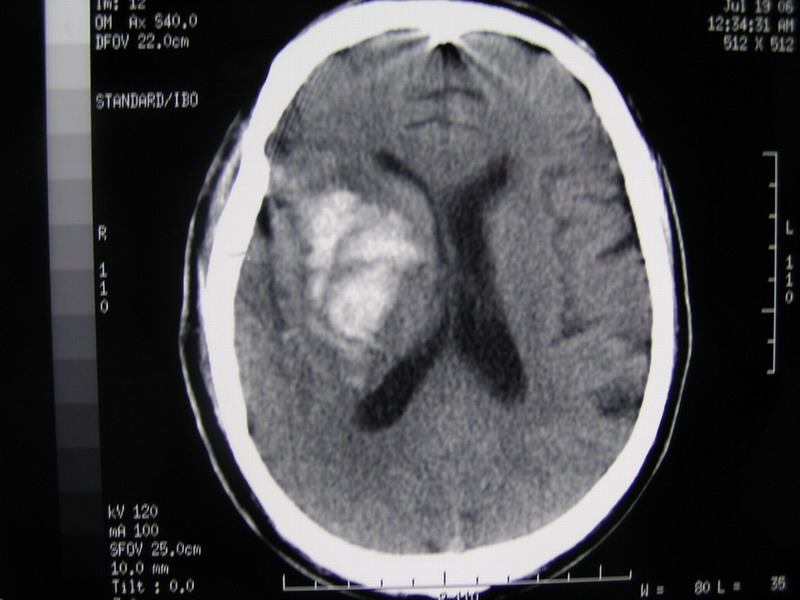

以下是引用13081830109在2007-4-3 22:44:00的发言:[br]感觉1:穿刺针为非专用的 不知是哪里生产的有专利证吗? [br] 2:穿刺点选择的往下了 该位置易引起继发性血肿[br] 3: 穿刺角度选择的往后了[br] 4: 侧孔位置不对 该位置在冲洗时极易抽出脑组织[br] 建议: 旋转穿刺针使侧孔向后方[br] 冲洗时用小注射器(5ml)以0.5压力为好[br] 尿激酶应用要慎重[br] 如患者病情允许不要用脱水药[br] [br][br][br][br]以上意见仅供参考[br]